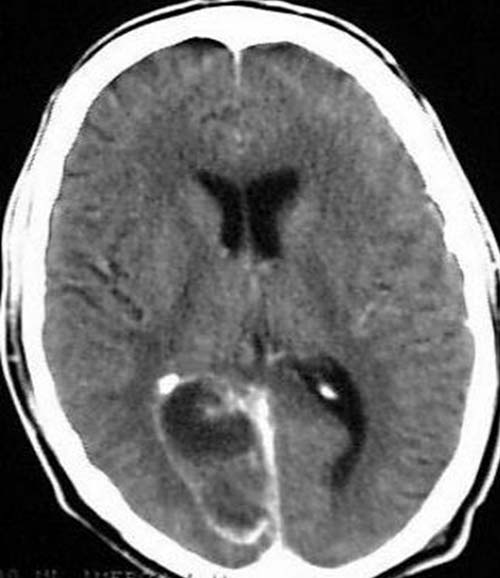

34 jähriger Patient wird mit Fieber eingeliefert. Homonyme Hemianopsie

nach links.

CCT mit Kontrastmittel.

Hypodense

Raumforderung occipital rechts. Kontrastmittel-aufnehmende Ringstruktur mit

diskreten hypodensen

Arealen um die Ringstruktur. Asymmetrie der

Hinterhörner.

Hirnabszeß mit

deutlich Kontrastmittel- aufnehmender

Abszeßmembran und wenig perifokalem Ödem mit konsekutiver

Kompression des rechten Hinterhorns.